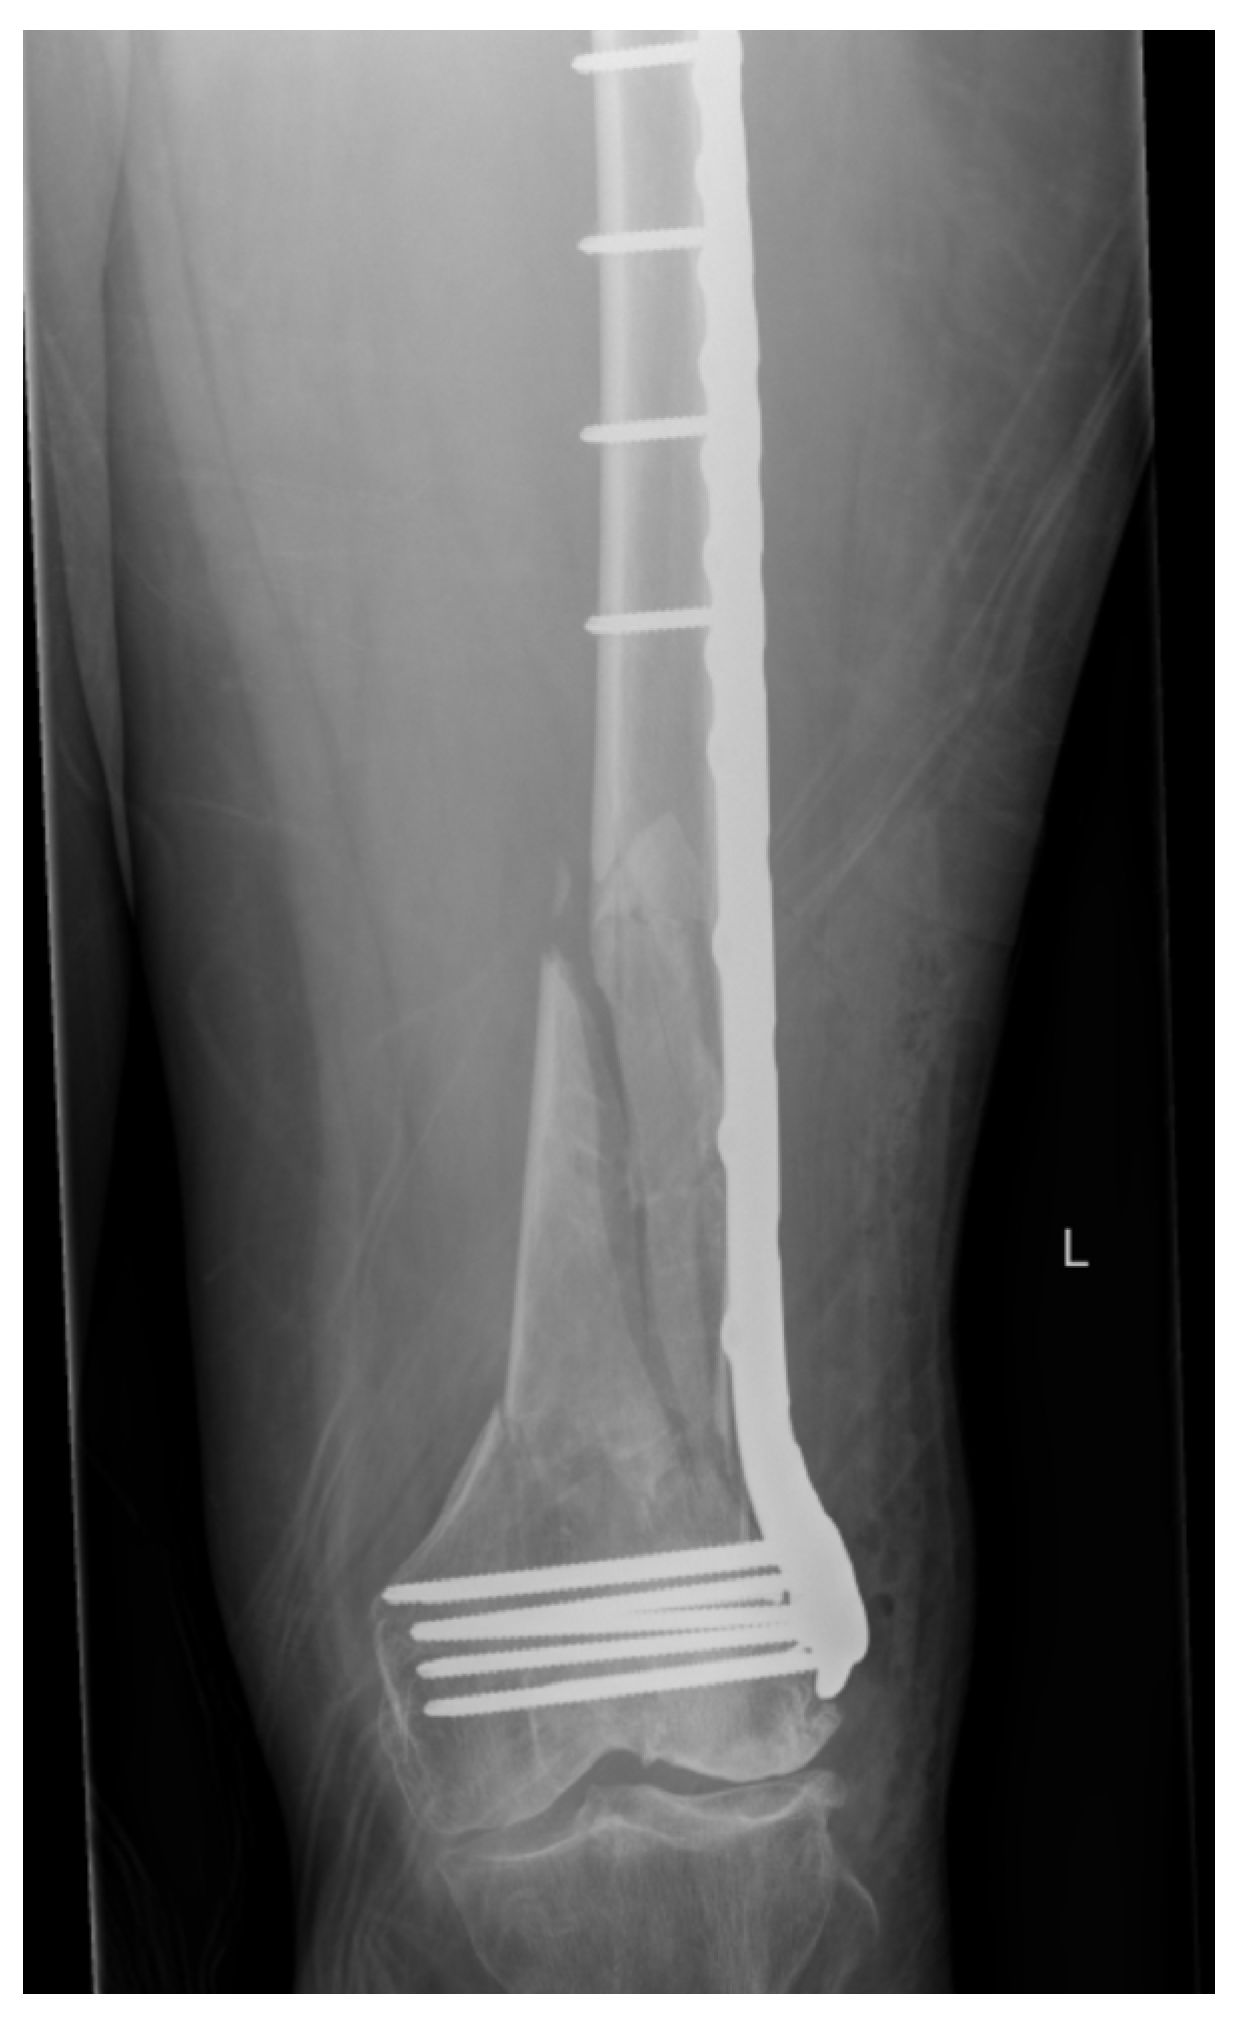

Nail–Plate Constructs for Treating Distal Femur Fractures: A Systematic Review of Biomechanical Studies

3.2. NPCs vs. DP Constructs

3.3. NPCs vs. DLFLP

3.4. NPCs vs. Parallel Plating and Orthogonal Plating

3.5. NPCs vs. Retrograde Intramedullary Nail

3.6. NPCs Using Variable Nail Size

3.7. Linked NPCs vs. Non-Linked NPCs